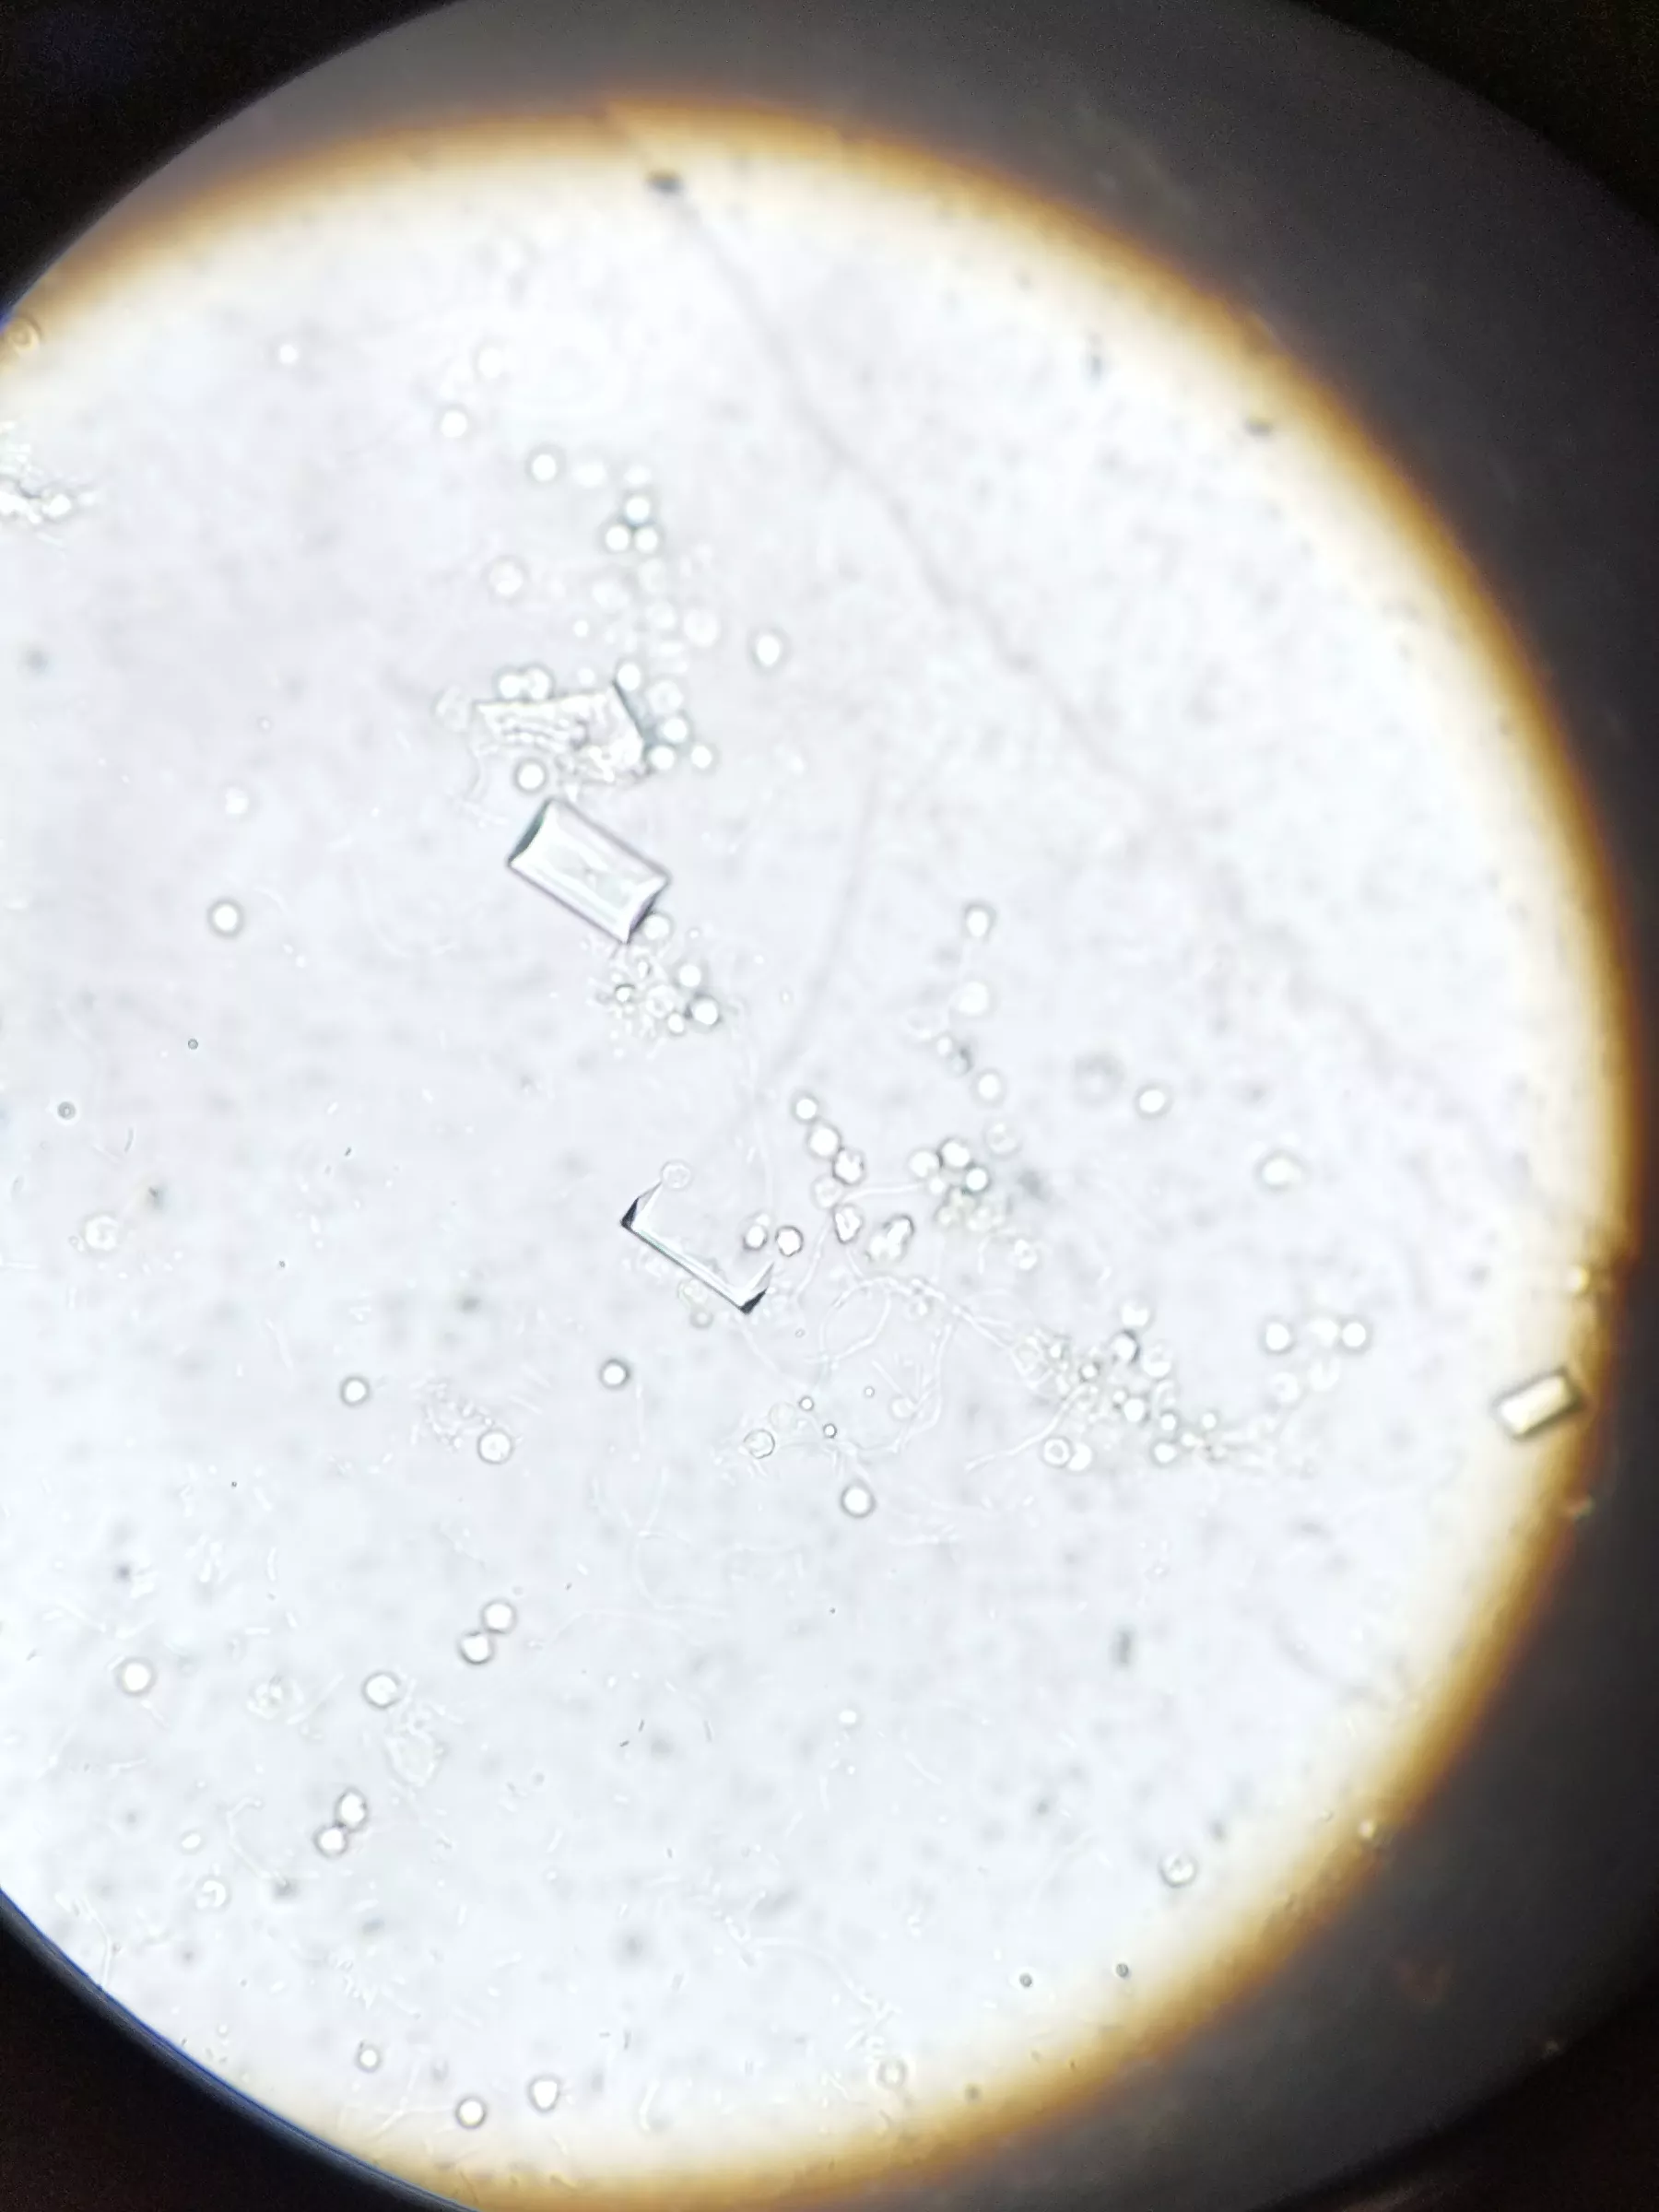

- Análisis clínicos: Análisis de sangre, orina y otros estudios de laboratorio que nos permiten obtener un panorama detallado del estado de salud de tu compañero.